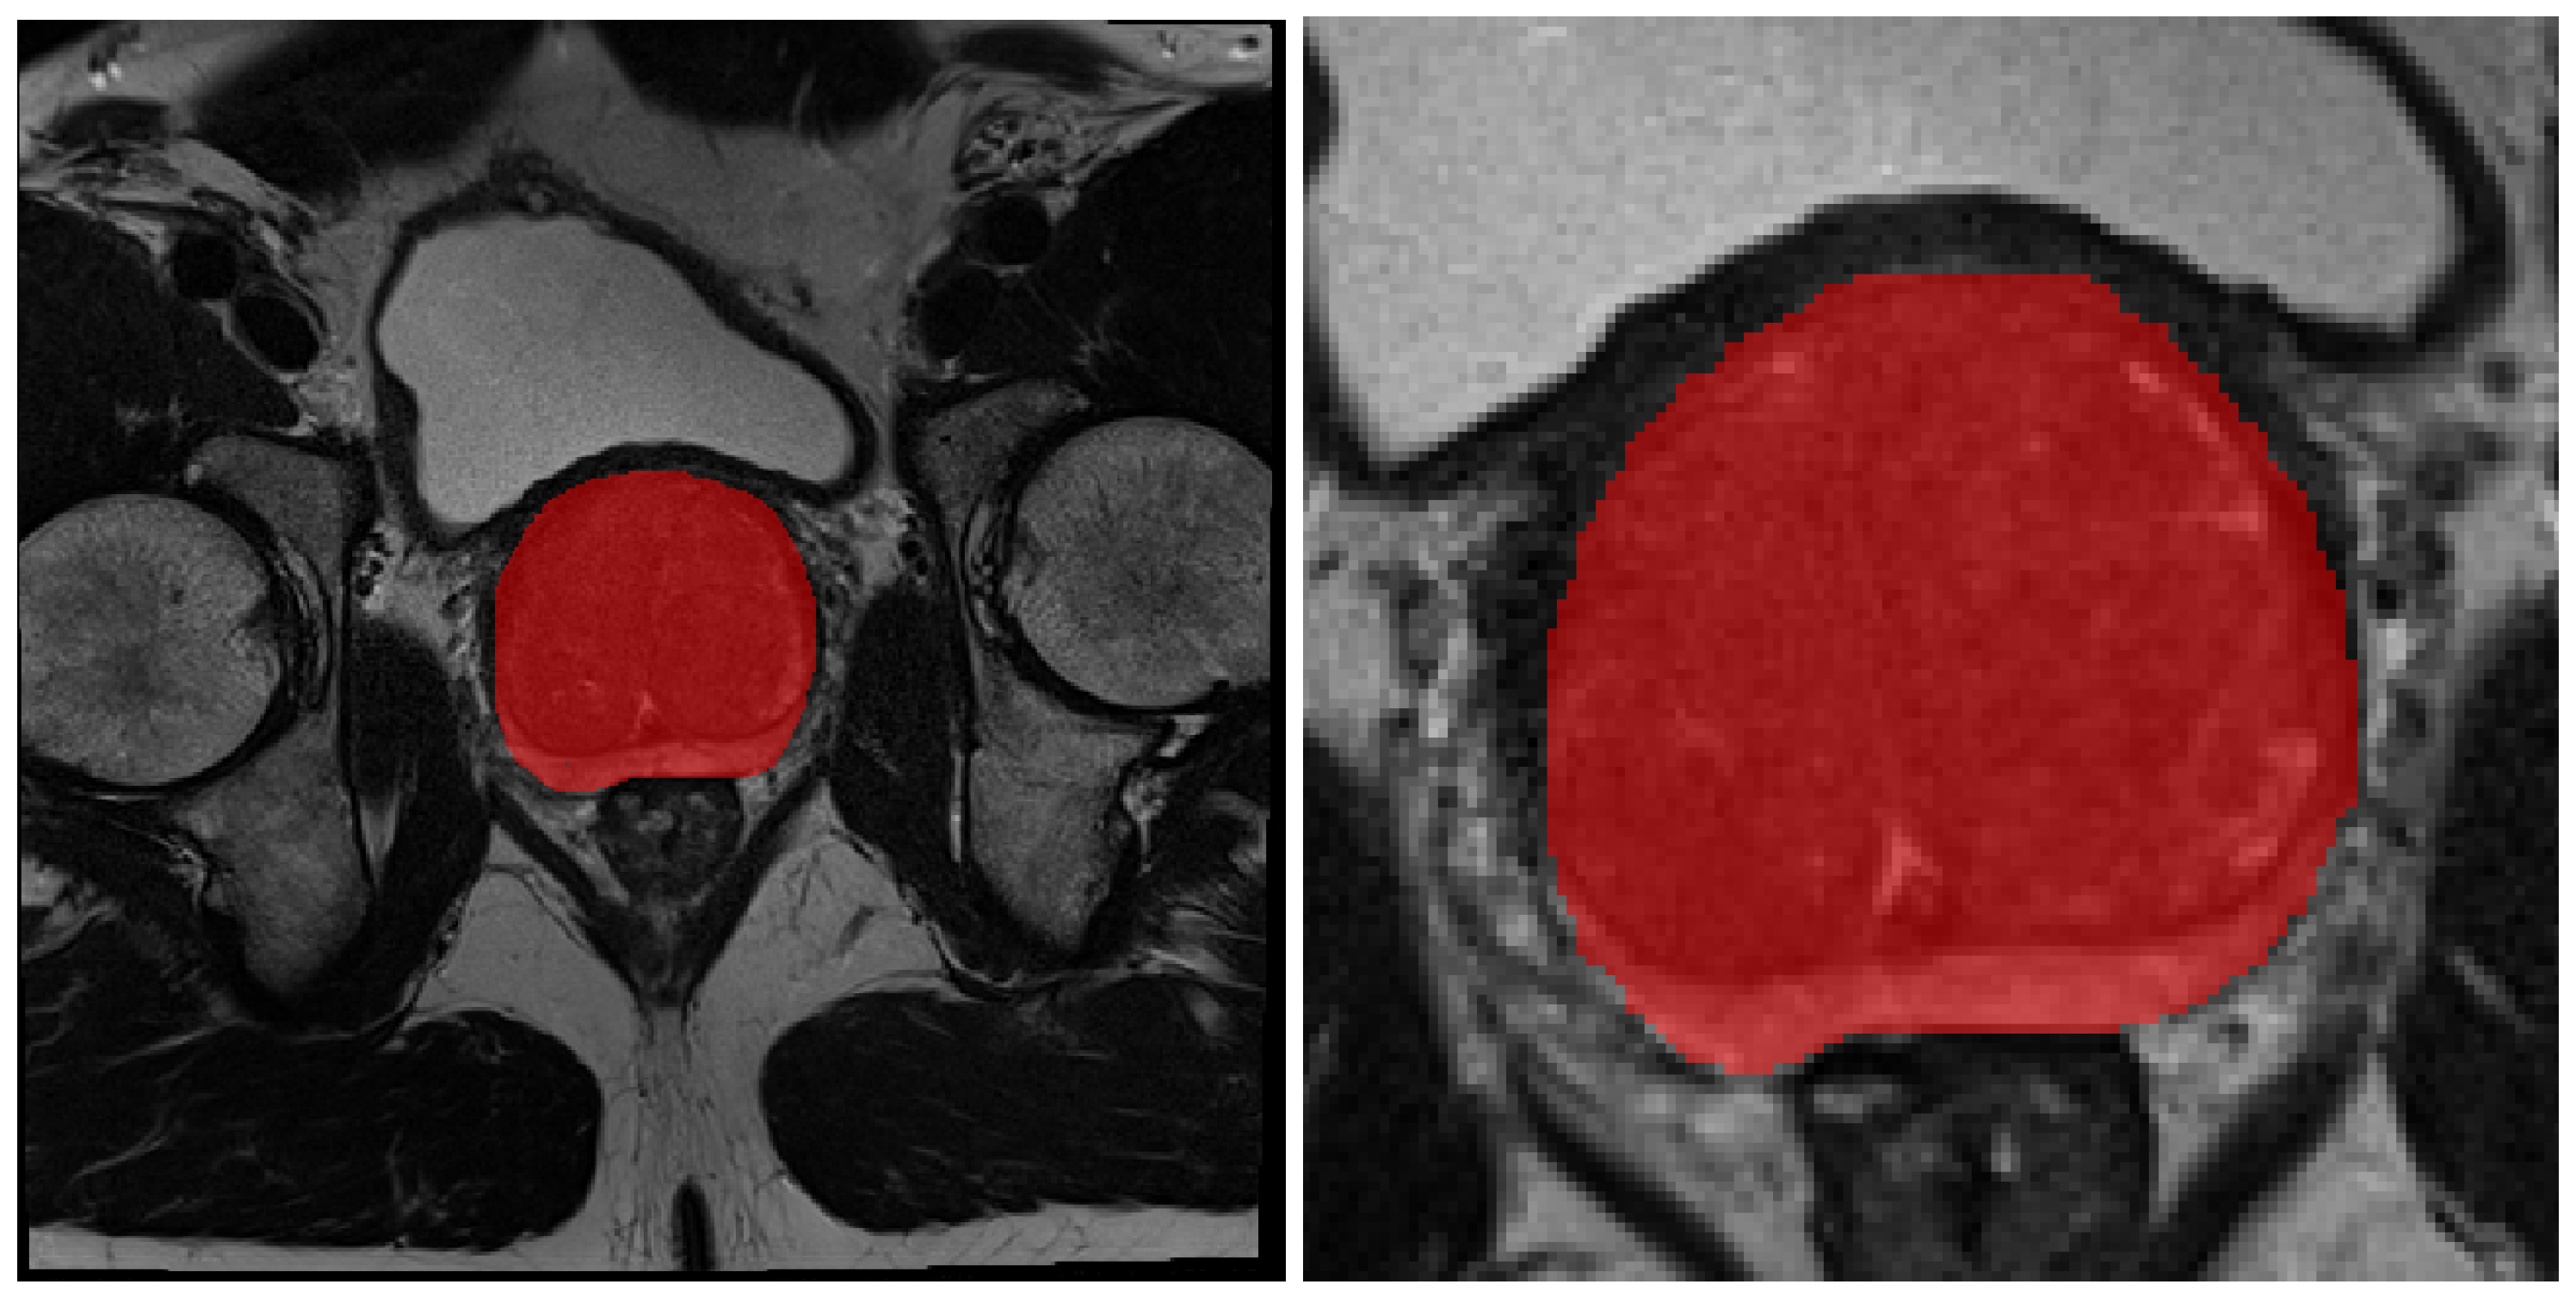

2.2. Prostate Detection

2.3. T2W Pre-Processing and Augmentation